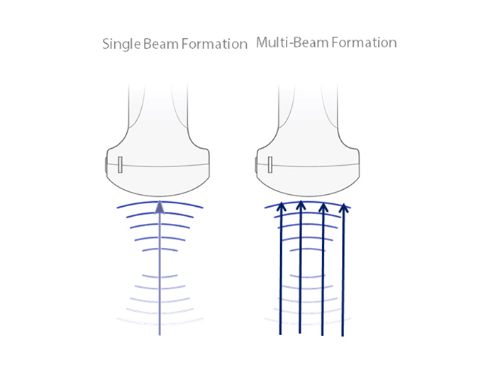

iBeamTM

Permits use of multiple scanned angles to form a single image, resulting in enhanced contrast resolution and improved visualization.